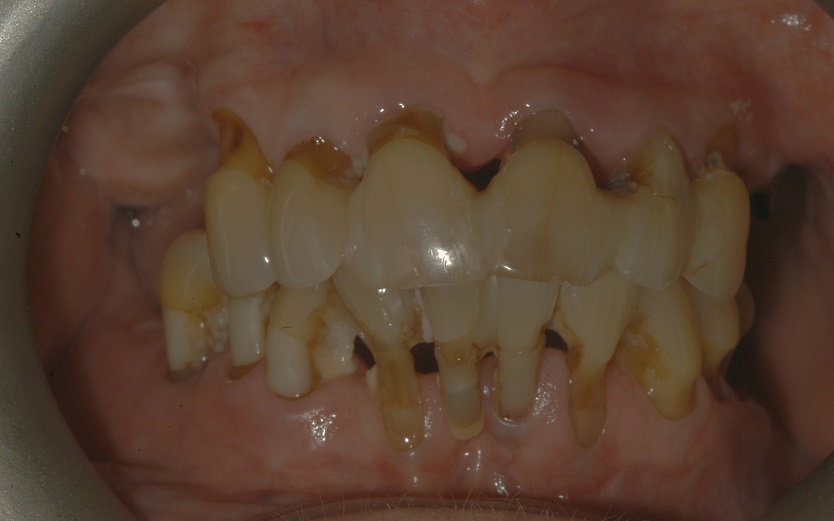

BEFORE + AFTER

Before BarZero LTP Installation